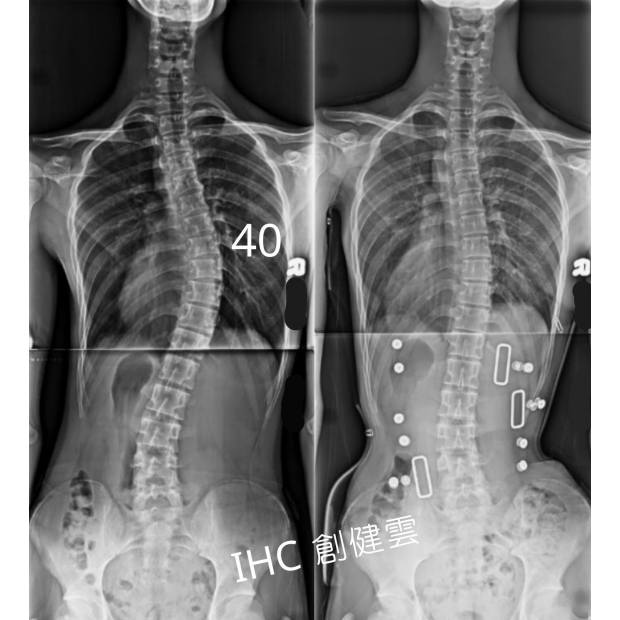

15歲脊椎側彎男孩

胸彎40度